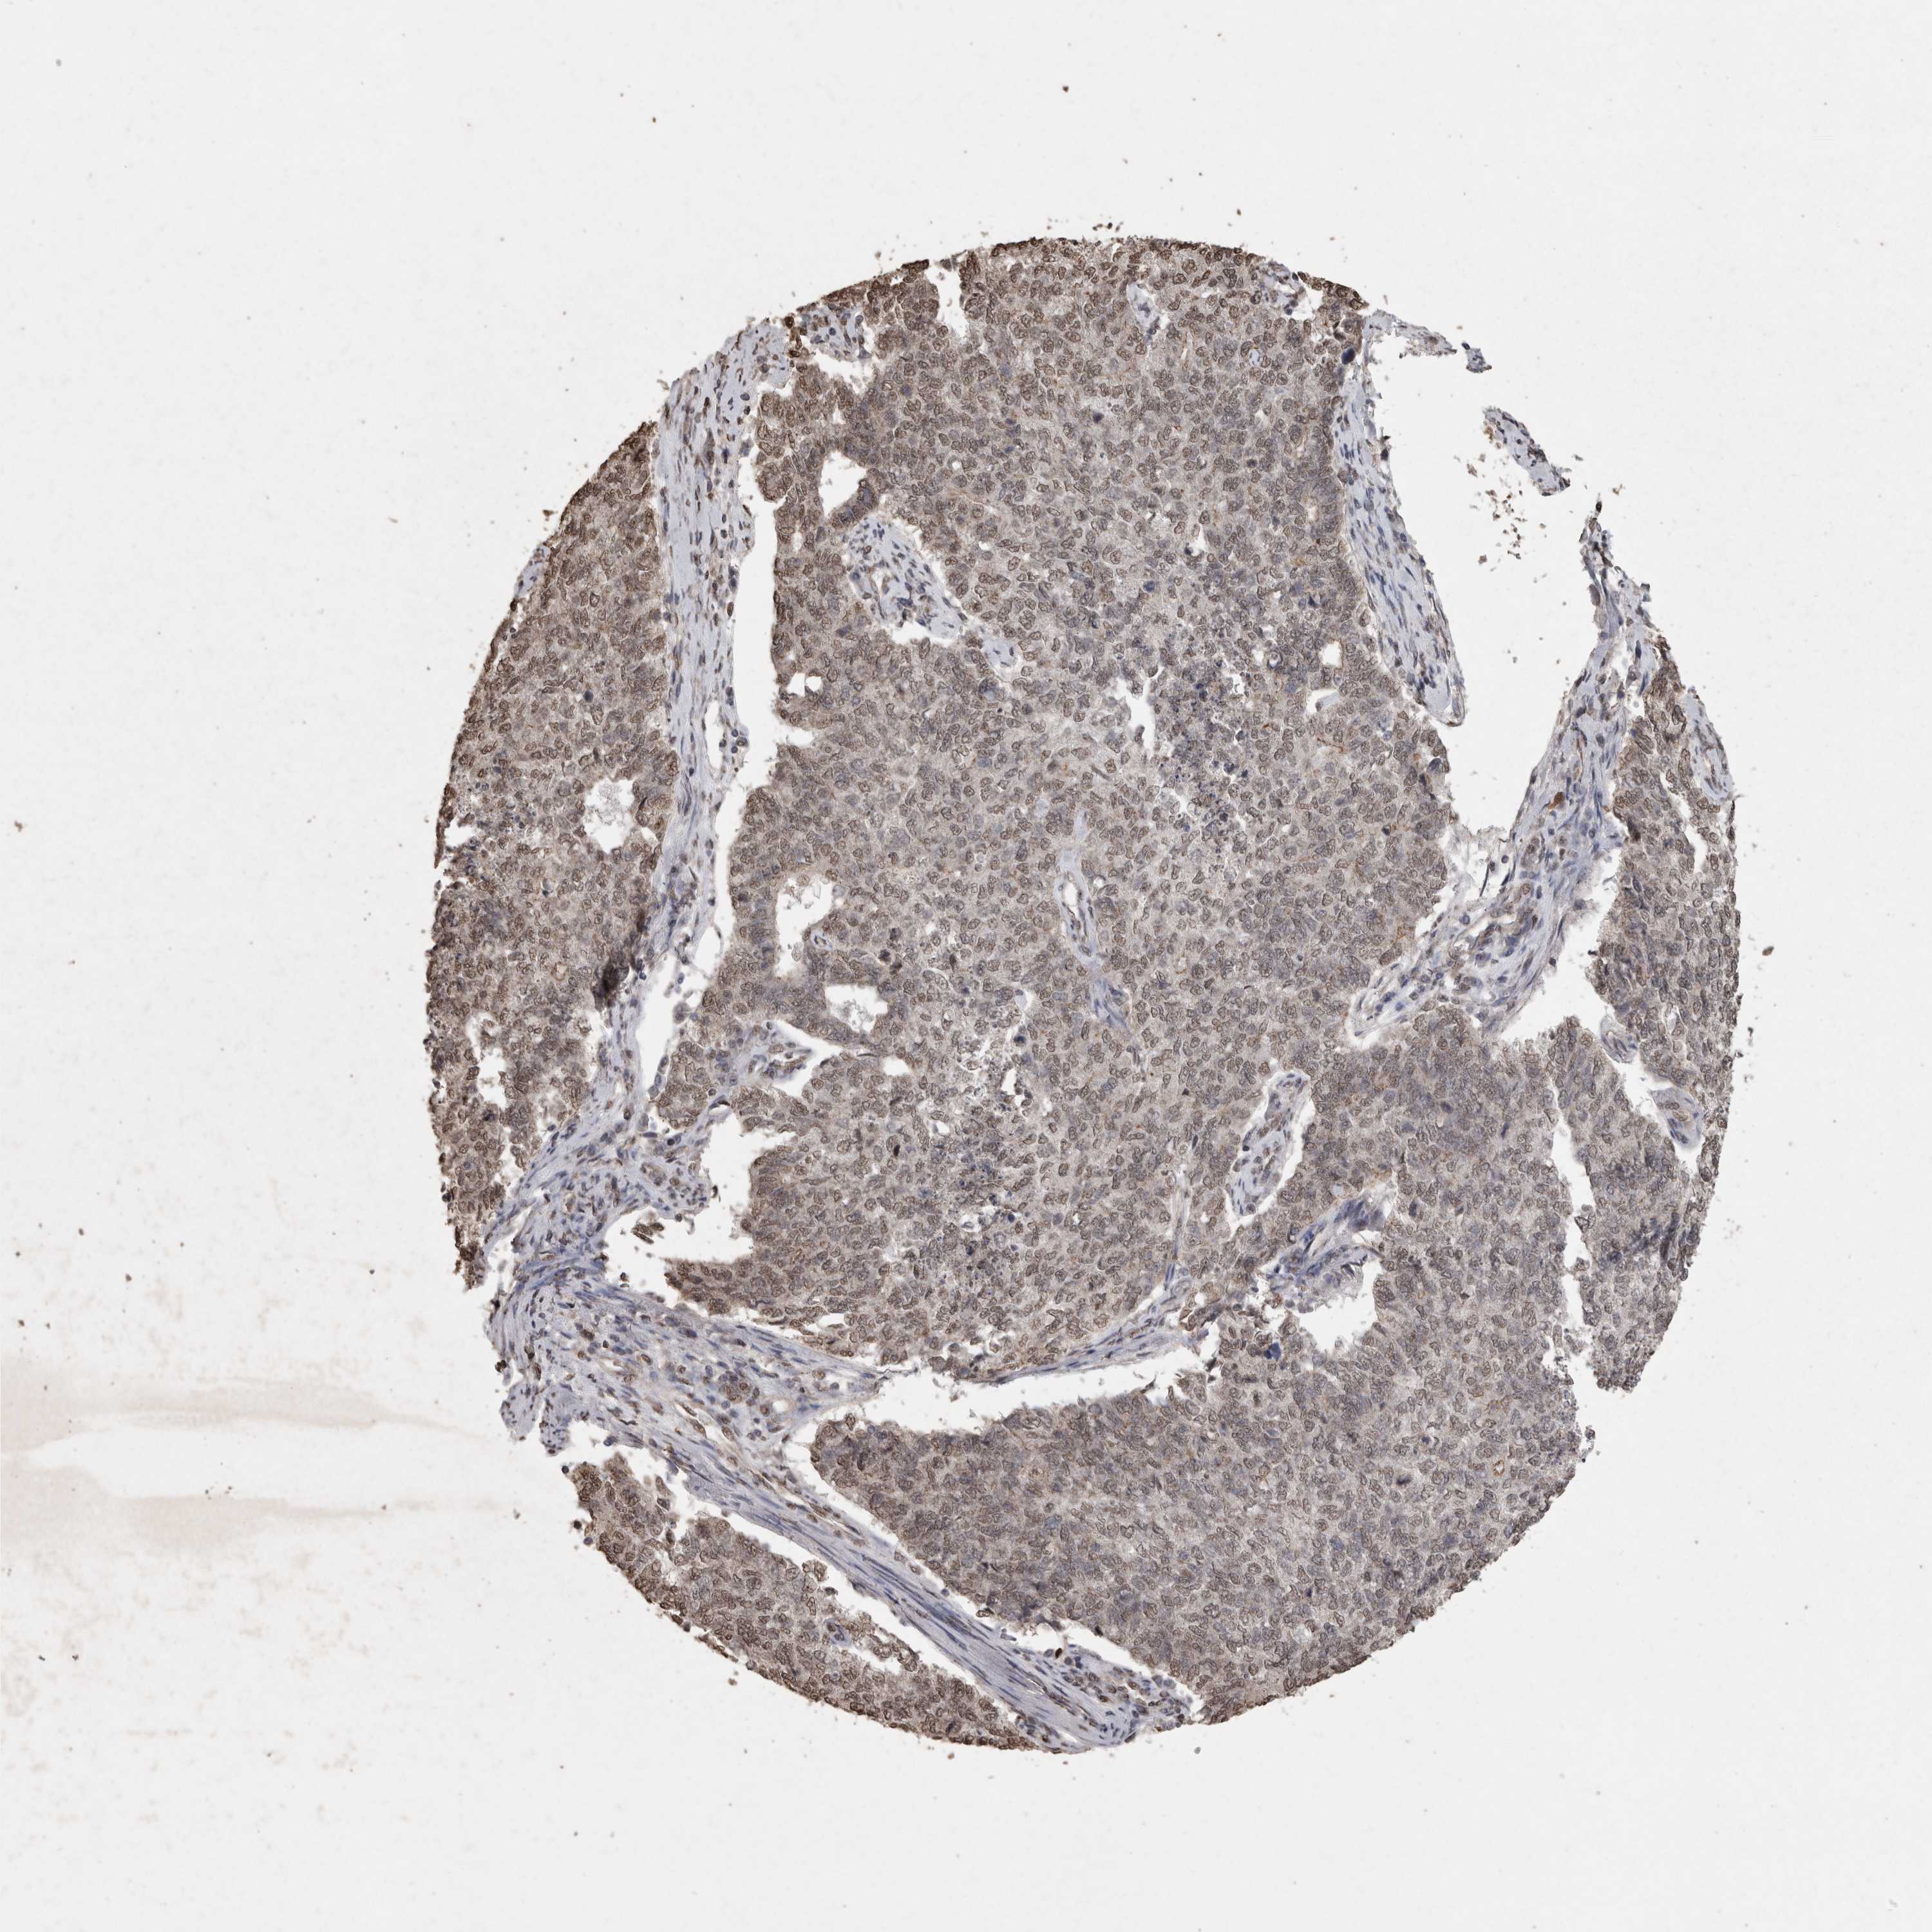

CERVICAL CANCER - Protein expressioni

A mouse-over function shows sample information and annotation data. Click on an image to view it in a full screen mode. Samples can be filtered based on level of antibody staining by selecting one or several of the following categories: high, medium, low and not detected. The assay and annotation is described here.

Note that samples used for immunohistochemistry by the Human Protein Atlas do not correspond to samples in the TCGA dataset.

Antibody stainingi

Antibody staining in the annotated cell types in the current human tissue is reported as not detected, low, medium, or high, based on conventional immunohistochemistry profiling in selected tissues. This score is based on the combination of the staining intensity and fraction of stained cells.

Each image is clickable and will lead to virtual microscopy that enables deeper exploration of all samples and also displays staining intensity scores, fraction scores and subcellular localization as well as patient and tissue information for each sample.

Antibody HPA028897

Antibody CAB026212

Staining

High

Medium

Low

Not detected

Intensity

Strong

Moderate

Weak

Negative

Quantity

>75%

75%-25%

<25%

None

Location

Nuclear

Cytoplasmic/membranous

Cytoplasmic/membranous,nuclear

Adenocarcinoma, NOS